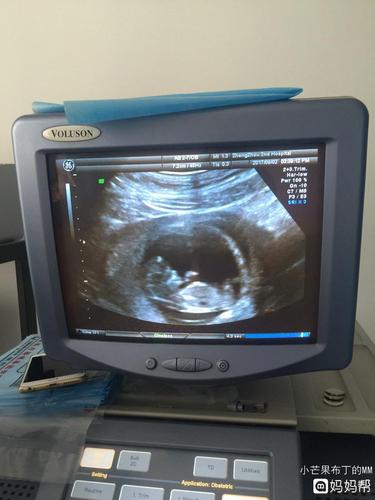

![11周胎儿图男孩子,怀孕11周男孩b超图 13楼 2015-7-3 孕11周 2小宝宝好可爱[爱心]心率170/分好快的呢](https://ss3.baidu.com/-fo3dSag_xI4khGko9WTAnF6hhy/zhidao/pic/item/d01373f082025aaf24f82158fdedab64024f1a5e.jpg)

13楼 2015-7-3 孕11周 2小宝宝好可爱[爱心]心率170/分好快的呢